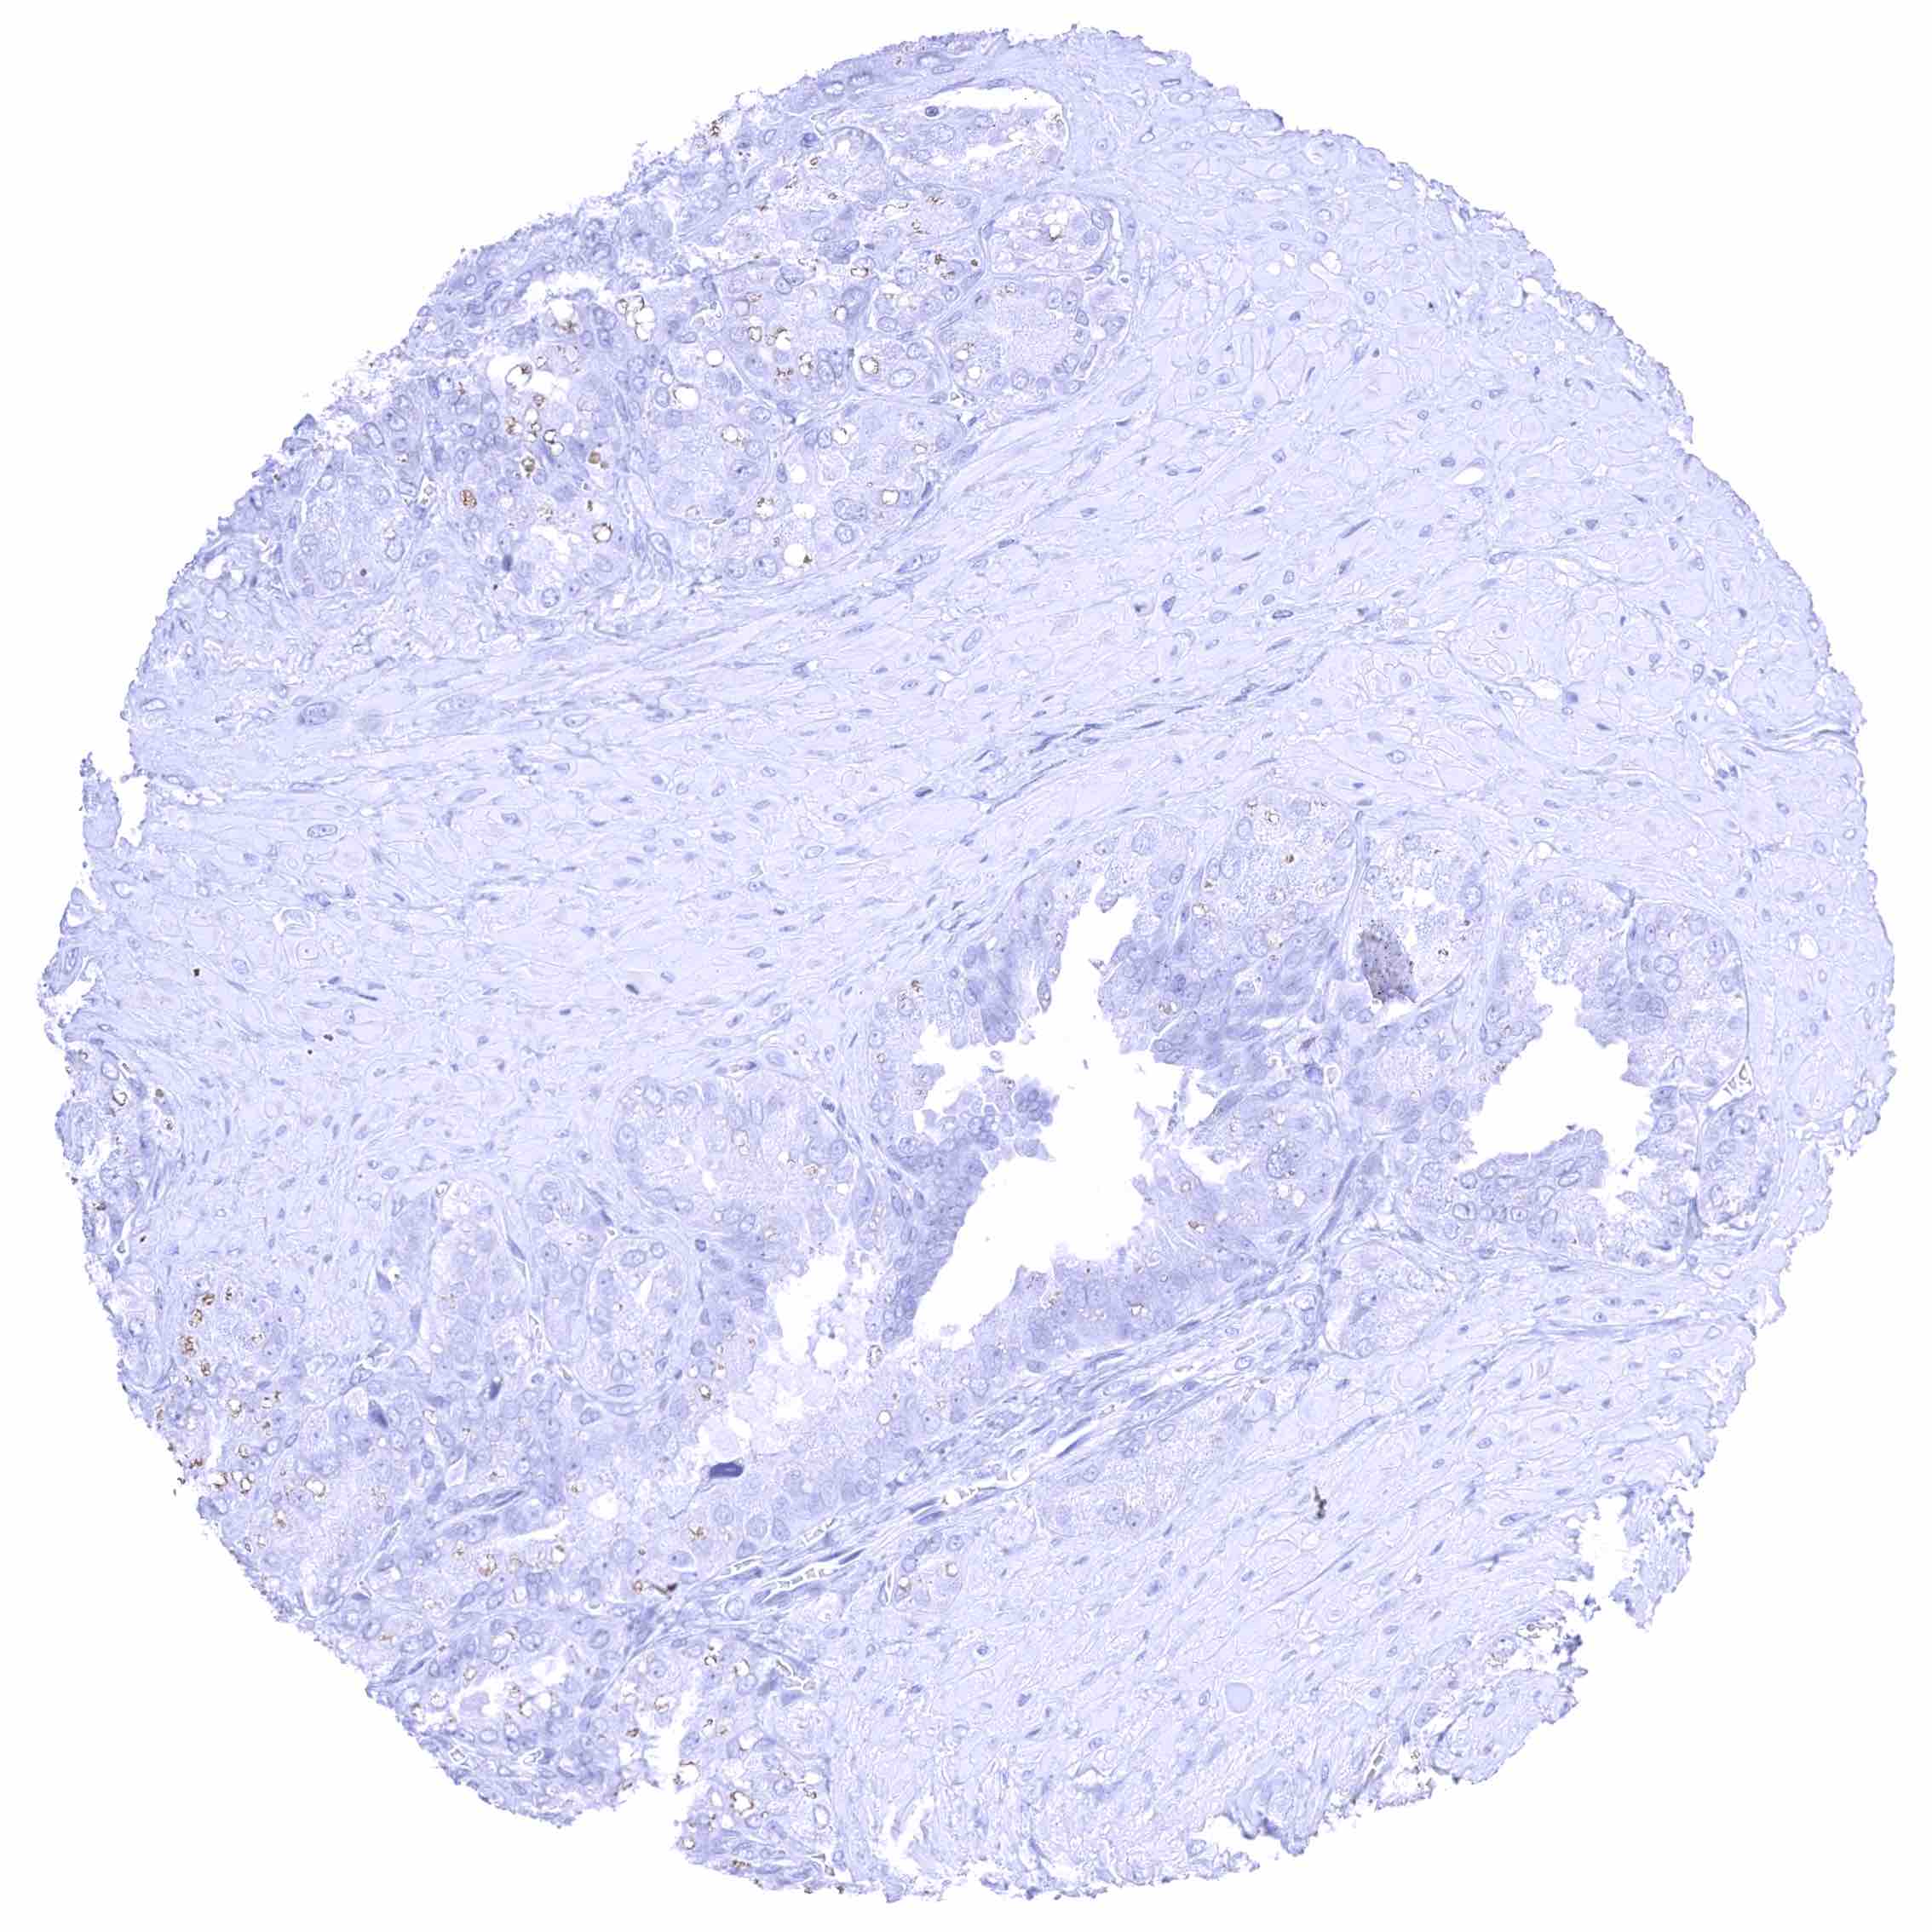

Prostate